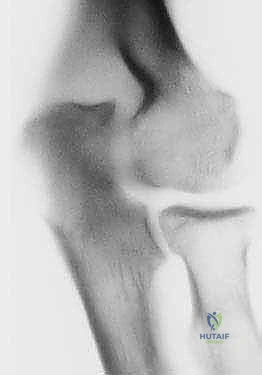

- الأشعة السينية (X-rays): الفحص الأساسي لرؤية العظام. تُظهر الأشعة السينية بوضوح تضيق المسافة المفصلية، وجود النتوءات العظمية (المهماز العظمي) في الحفرة الزجية والإكليلية، والأجسام الحرة الكبيرة.

- الأشعة المقطعية ثلاثية الأبعاد (3D CT Scan): تُعد الأداة الأهم للتخطيط الجراحي لعملية أوتبيردج-كاشيواجي. توفر خريطة دقيقة ثلاثية الأبعاد لحجم وموقع النتوءات العظمية، وتساعد الدكتور هطيف على تحديد كمية العظام التي يجب إزالتها بدقة مليمترية.